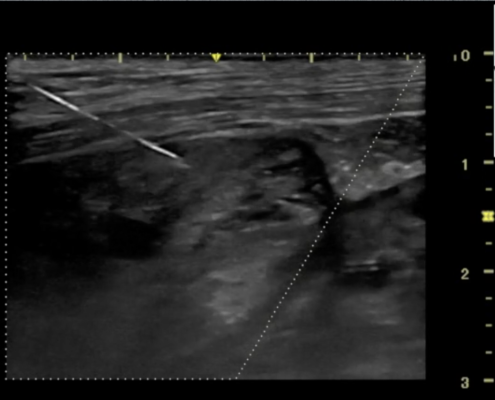

Servet, como Centro de Referencia, se mantiene al día de todas las novedades que afectan al desarrollo de nuestras actividades, con dos objetivos principales, mejorar la formación del personal clínico e incorporar los medios tecnológicos más avanzados. Esto nos permite mejorar el bienestar de los animales atendidos.